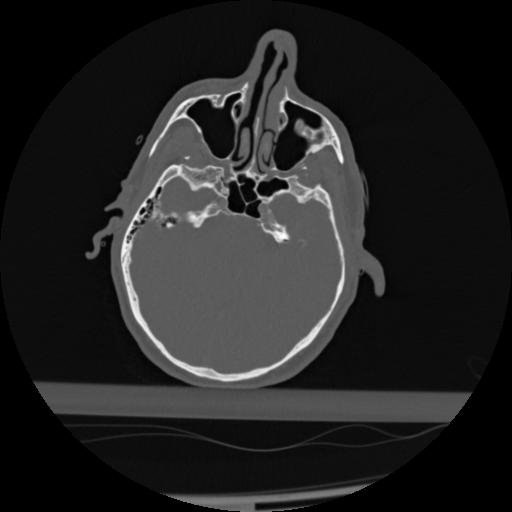

22 ANGIO,CE,Vol,0.5,ANGIO,,